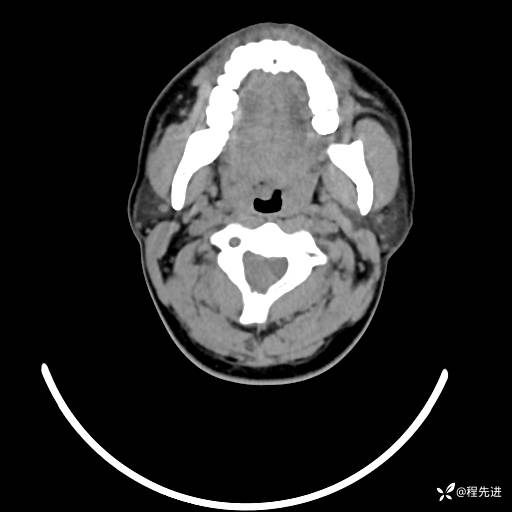

CT平扫+增强: